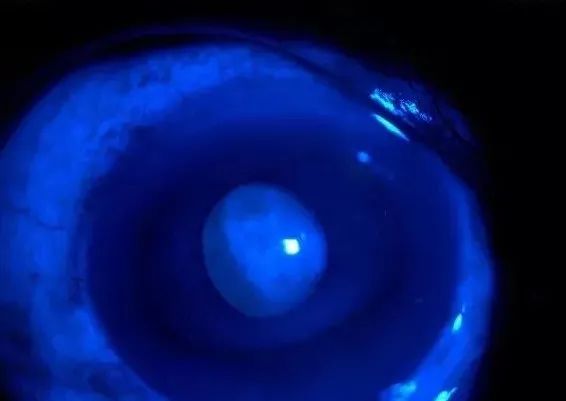

4、滤光式投照法

滤光式投照法和弥散式投照法比起来,光源变成了钴蓝光源,物镜中加了黄色滤光镜(这一点在国内很多地方都省略了),同时,眼内滴入了荧光素钠滴眼液。从而提高对比度,使图像更加清晰。荧光素染色更常用观察角膜病变,这种方它可以清楚的勾勒出角膜损伤的范围,深度,帮助医生了解病情。同时,在硬镜包括角膜塑形镜的验配评估中发挥了重要作用。

病毒性角膜炎